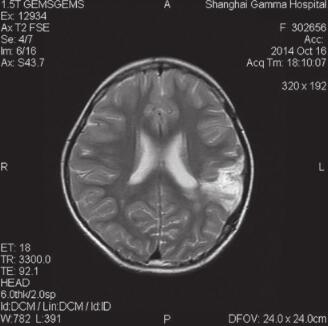

3.患者2014年10月16日放疗后一个月复查MRI(图4)提示:病情稳定。

图4 2014-10-16放疗后一个月复查MRI提示:病情稳定